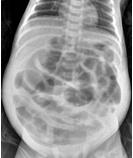

新生兒壞死性小腸結腸炎癥

• 新生兒壞死性小腸結腸炎